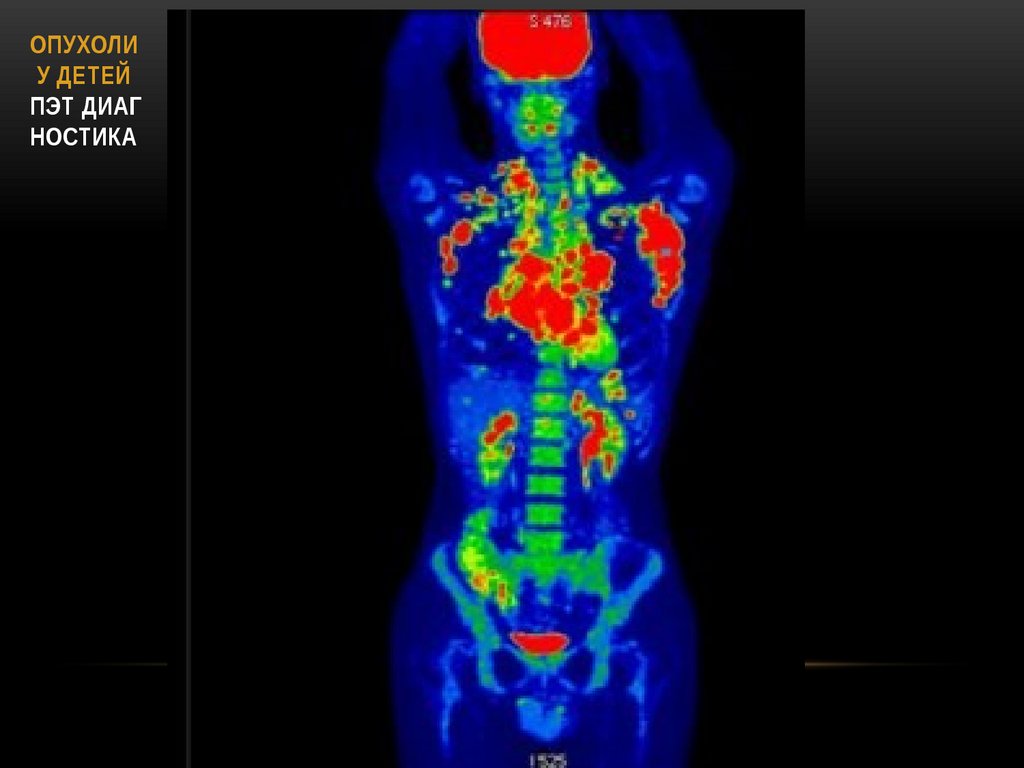

46. ОПУХОЛИ У ДЕТЕЙ ПЭТ диаг ностика

ОПУХОЛИ

У ДЕТЕЙ

ПЭТ ДИАГ

НОСТИКА